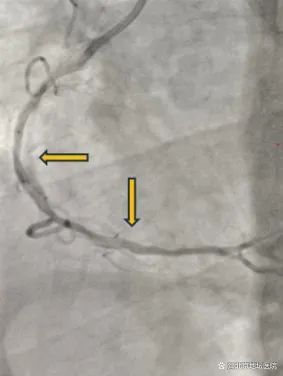

治疗前

“Shockwave冲击波球囊就位,工作压力4atm,释放脉冲!6atm,释放脉冲!”按照预定方案,管浩副主任对病变血管进行治疗,扩张6次后撤出冲击波球囊。复查OCT显示病变预处理充分,随后在右冠脉病变处植入两枚支架,经OCT再次评估支架贴壁良好,冠脉造影示支架展开良好,效果满意。术后,经过医护团队的精心治疗,陈大爷恢复健康,顺利出院。它对管浩副主任医师带领心内科团队的精湛医术和“新武器”——Shockwave冲击波球囊表示认可。